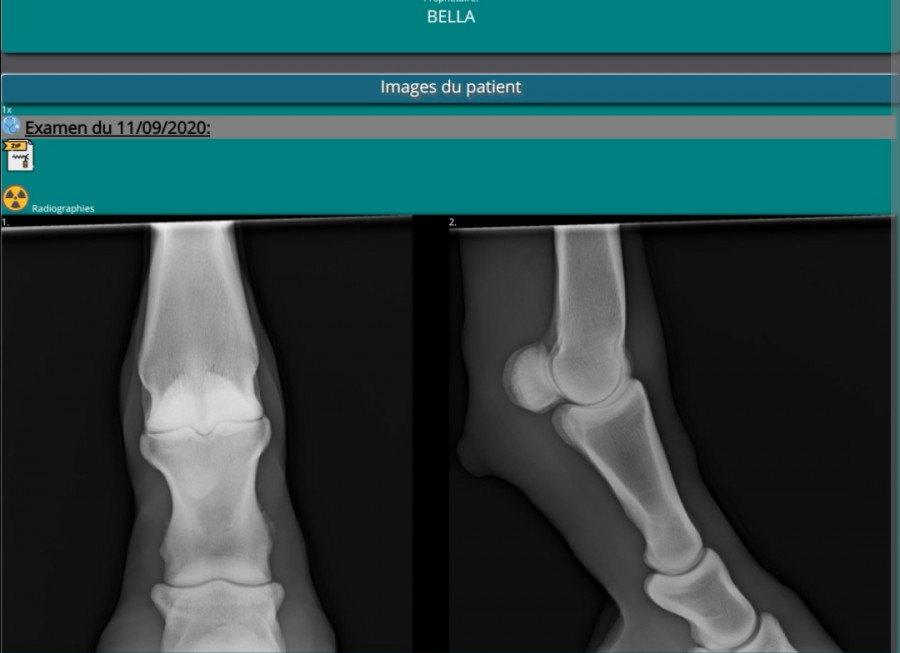

La vétérinaire spécialisée en locomotion vient de passer. Radio faite : entorse du paturon!

Un mois de box strict minimum. Contrôle dans 1 mois. Sous anti inflammatoire 10 jours et crème anti inflammatoire 15 jours.

Mais d'après ce que j'ai compris, sur la radio, il n'y avait rien de sévère, elle disait que l'entorse avait évolué dans le bon sens. Elle veut surtout qu'elle ne fasse pas d'arthrose dessus. Au trot elle ne boîte quasi plus, au pas plus du tout. Le fait de l'avoir remise avec les autres il y a 10 jours n'a pas aggravé sa lésion visiblement, d'autant plus qu'elle boîte de moins en moins.

Si, à la radio elle a vu tout de suite l'entorse. Ce qui est décrit sur son compte rendu finalement.

Elle disait que ça s'était amélioré car sa démarche c'était grandement amélioré, qu'il y avait pas eu d'évolution défavorable lorsqu'on l'avait remise au paddock paradise avec ses copains. Et sur la radio c'était pas une entorse importante, mais elle a peuf qu'elle fasse de l'arthrose dessus si on ne l'immobilise pas.

Voici les radios si ça peut servir

La veto me montrait les "traits" en fondu sur le côté de l'os